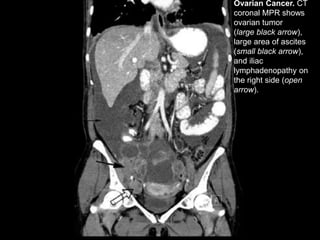

Ovarian Cancer. CT

coronal MPR shows

ovarian tumor

(large black arrow),

large area of ascites

(small black arrow),

and iliac

lymphadenopathy on

the right side (open

arrow).